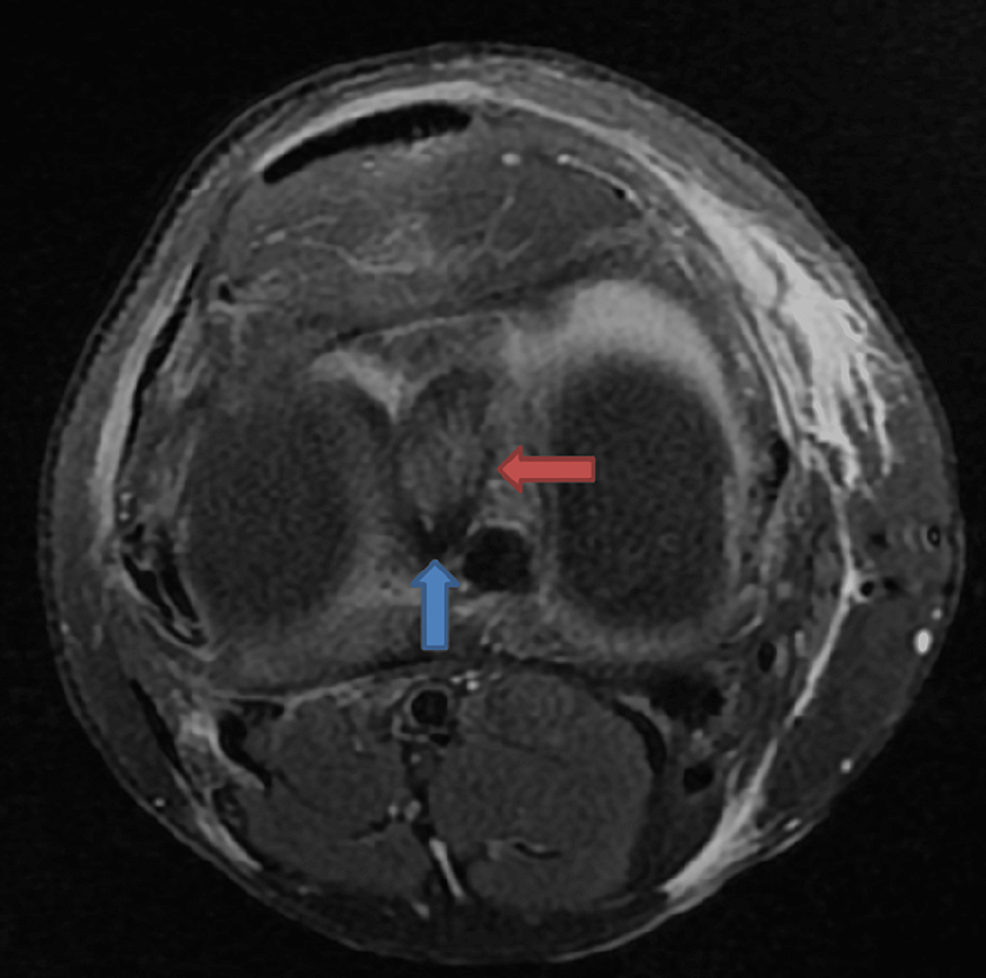

Double PCL sign of meniscal bucket handle tear Image Bucket Handle Tear In Mri This kind of injury often happens when you. Diagnosis can be suspected clinically with joint line tenderness and a positive mcmurray's test, and can be confirmed with mri studies. Displacement of meniscal tissue is an indirect sign of a meniscal tear and can present with symptoms of joint locking and clicking. A bucket handle meniscus tear is an injury to. Bucket Handle Tear In Mri.

Double PCL sign appears on sagittal MRI images of the knee when a Bucket Handle Tear In Mri Displacement of meniscal tissue is an indirect sign of a meniscal tear and can present with symptoms of joint locking and clicking. Diagnosis can be suspected clinically with joint line tenderness and a positive mcmurray's test, and can be confirmed with mri studies. This kind of injury often happens when you. A bucket handle meniscus tear is an injury to. Bucket Handle Tear In Mri.